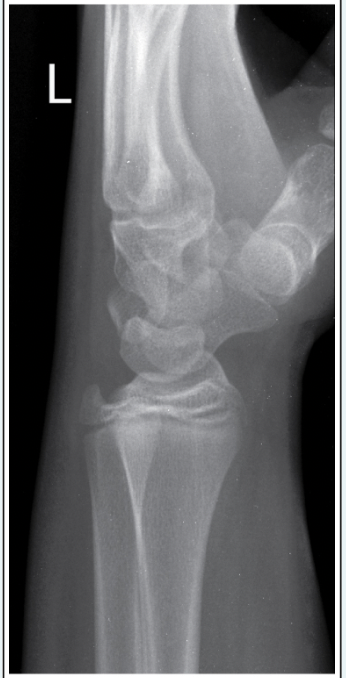

This AP elbow image demonstrates incorrect positioning of the part. What error occurred?

d.Humeral epicondyles are not parallel to the IR

How should this error be corrected on the repeat AP elbow image?

b.Arm should be rotated internally